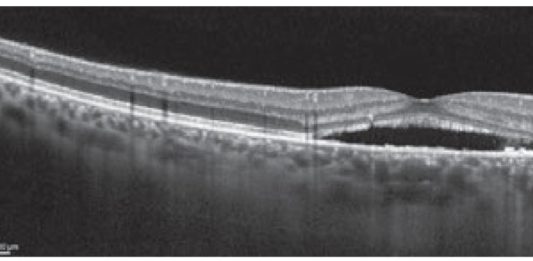

Una seria complicanza da vitreolisi

Una paziente di 61 anni giunse alla visita oculistica di controllo a marzo del 2015 lamentando la...